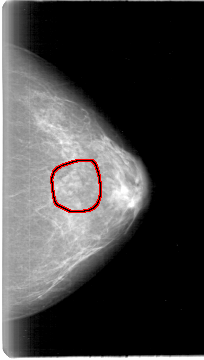

D_4024_1.LEFT_MLO

LEFT_MLO LINES 5386 PIXELS_PER_LINE 3076 BITS_PER_PIXEL 12 RESOLUTION 43.5 OVERLAY

FILE: D_4024_1.LEFT_MLO.OVERLAY

TOTAL_ABNORMALITIES 1

ABNORMALITY 1

LESION_TYPE MASS SHAPE LOBULATED MARGINS CIRCUMSCRIBED

ASSESSMENT 0

SUBTLETY 3

PATHOLOGY BENIGN

TOTAL_OUTLINES 1

BOUNDARY